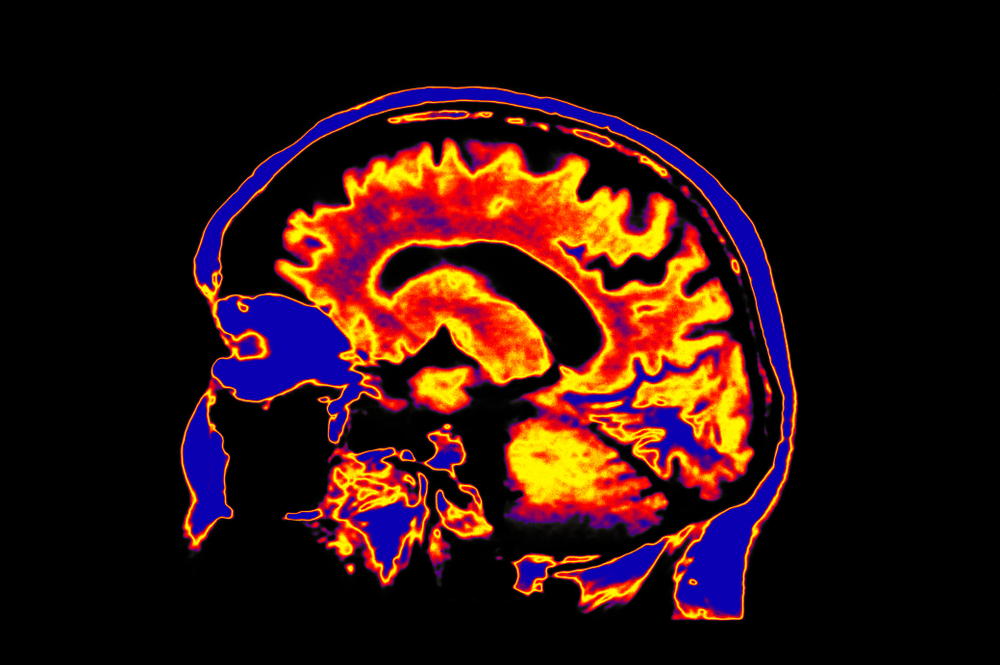

Every time you think, speak, or even prepare to say something, your brain sends a signal called a corollary discharge. This signal acts as a built-in “echo,” telling your brain that the sound or thought came from you. It helps your mind separate internal speech, like your thoughts, from actual sounds in the environment. In people with schizophrenia, this signal appears to be disrupted. Instead of recognizing the thought as self-generated, the brain perceives it as an external voice. Recent research from the University of New South Wales revealed that individuals with schizophrenia showed irregularities in how their brains processed this internal feedback system. The team used brain-imaging technology to track auditory responses and discovered that the corollary discharge mechanism was not functioning properly. As a result, the brain “hears” its own internal monologue as if it were coming from an outside source. https://youtu.be/PURvJV2SMso?si=WrucQtyavtGP9PZH This breakthrough helps explain one of schizophrenia’s most puzzling symptoms: auditory hallucinations. Understanding this mechanism gives scientists a clearer view of how disruptions in brain communication can alter perception and reality. It also shifts the focus from purely psychological theories to biological processes that can be measured, studied, and possibly treated. This research represents a turning point in how the medical community views schizophrenia. It shows that auditory hallucinations are not merely a product of imagination but a physiological error in brain signaling, a measurable glitch in the body’s communication system.How the Brain Misinterprets Its Own Thoughts

To understand how this malfunction leads to hearing voices, it helps to think of the brain as a conversation system. In a healthy brain, when you prepare to speak, neurons in the auditory cortex receive a “heads-up” signal predicting the sound of your own voice. This signal suppresses the brain’s response, preventing confusion between internal speech and external sounds. In schizophrenia, that suppression fails to occur. The auditory cortex becomes overly active, responding to self-generated thoughts as if they were external. According to a study published in Proceedings of the National Academy of Sciences, this breakdown in predictive signaling can make a person’s inner voice sound alien or threatening. Over time, this can lead to persistent hallucinations that deeply affect daily life and social interaction.